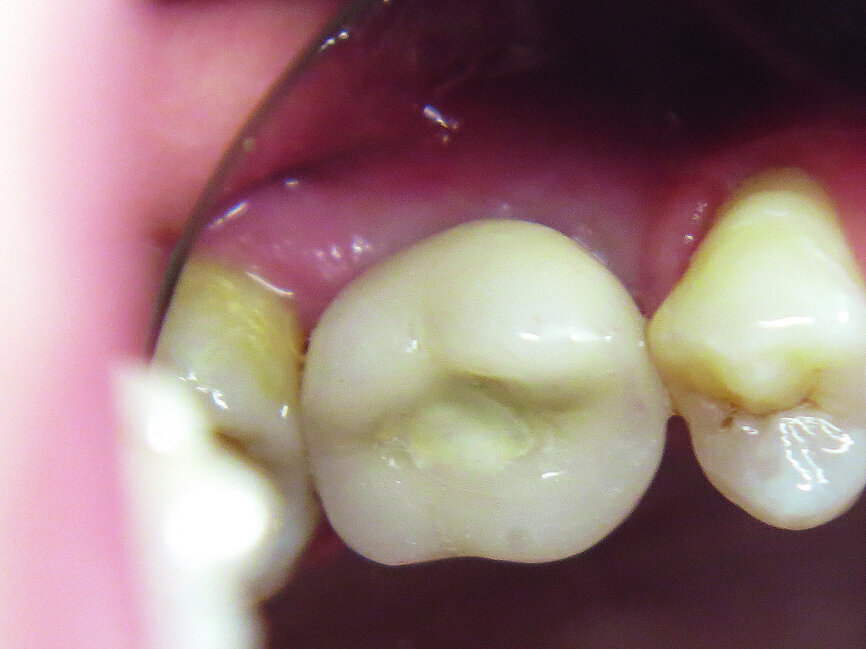

Fig. 1: Initial situation: severe bone defects and implant in situ.

The first was a 51-year-old patient who smoked 30 cigarettes per day and suffered from diabetes and stress (Figs. 1–8). The second was a 76-year-old male patient in good physical condition who smoked 40 cigarettes per day. He underwent reconstruction of the premaxilla (Figs. 9–13). The third was a healthy female patient of 24 years of age who smoked 20 cigarettes per day. She required a sinus lift in region #25 (Figs. 14–21). The patients were informed of the intended process in detail and signed the surgical protocol containing information concerning possible risks of failure and complications, as well as information on the alloplastic and synthetic materials to be used.